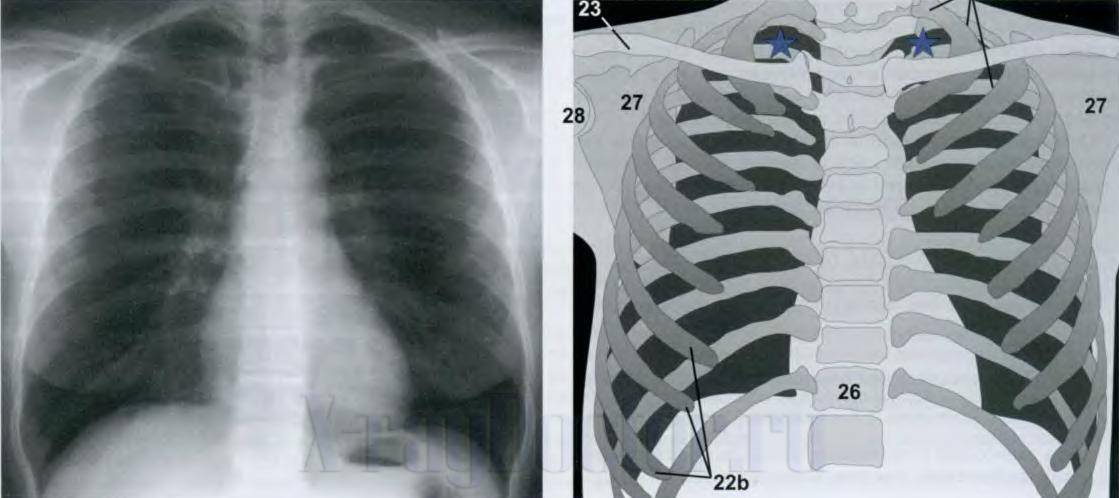

Чтобы читать рентген-снимки легких, изучить следует структурные элементы грудной клетки: легочные поля, средостение и костный остов. При подготовке врачей-рентгенологов в Ленинградской школе профессора применяли практический подход и рекомендовали врачу на начальных этапах смотреть максимальное количество нормальных снимков легких. Затем они должны были на ощупь определить, какой анатомический элемент скелета у них в руках. Только через несколько месяцев можно было приступать к изучению рентгенологических синдромов. В ускоренном курсе обучения предлагаем изучить структурные составляющие рентгенограммы органов грудной клетки по схеме (см. рисунок).

Схема чтения рентген-снимка легких и схематическая рентгеноанатомия (по Хоферу), где 23 – ключицы, 27 – лопатки, 26 – позвоночник, 22b – ребра. Темные участки справа и слева грудной клетки – легочные поля (в них при патологии появляются белые участки)

Как читать рентгеновские снимки позвоночника

На вышеприведенном рисунке под номером 26 изображен позвоночник. На рентгеновском снимке он представлен интенсивными тенями позвонков, между которыми светлые участки – межпозвонковые диски, которые имеют хрящевую структуру, поэтому не поглощают рентгеновские лучи. При патологических изменениях вертикальная ось может: